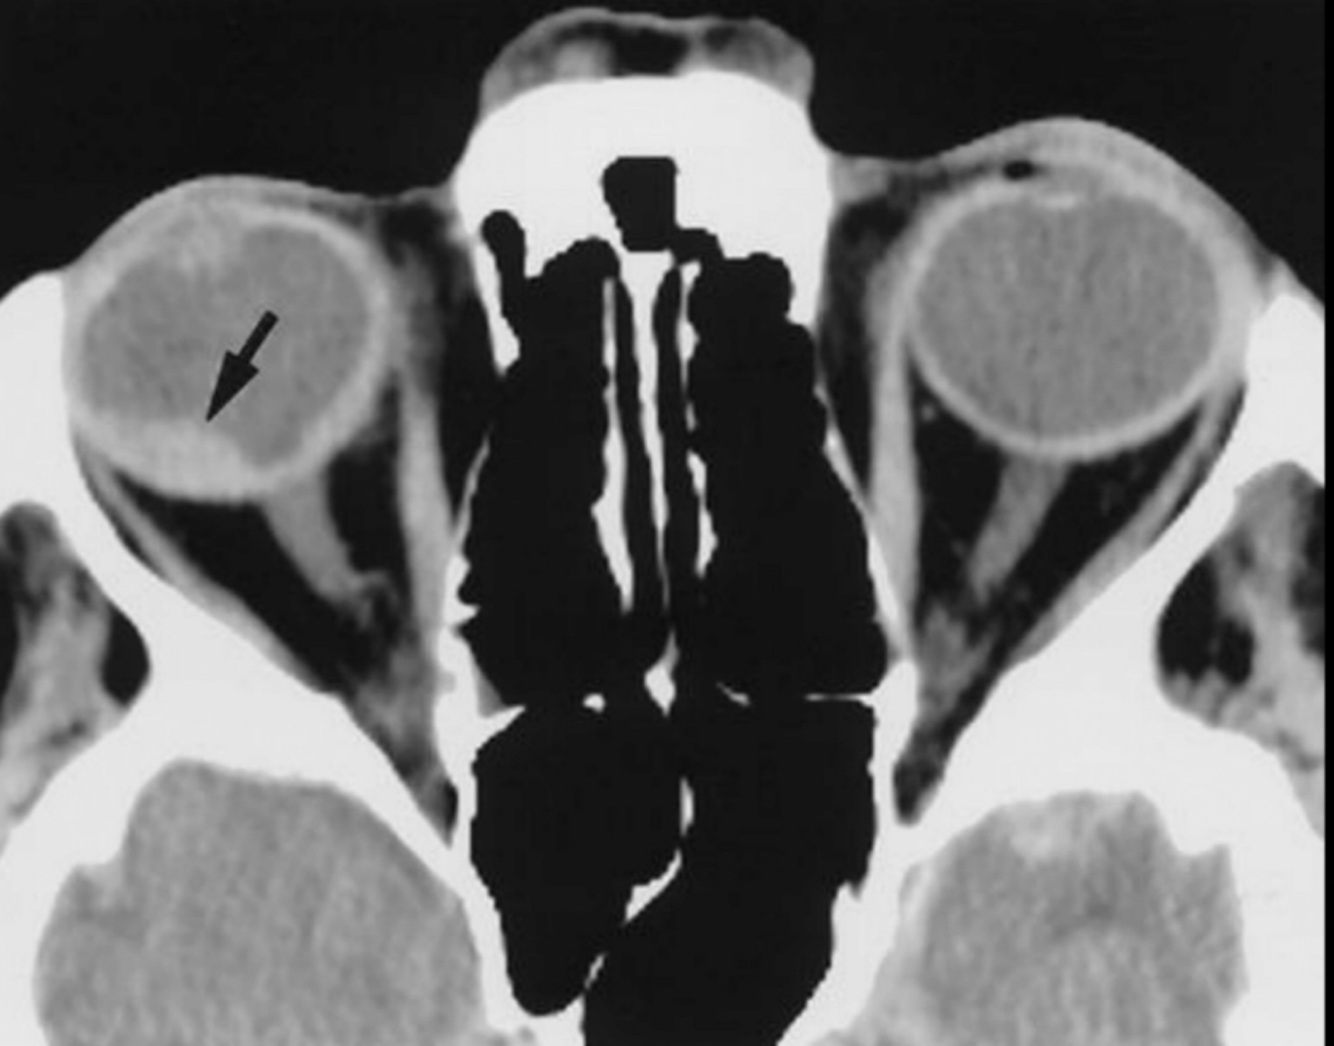

Hallazgo principal en orbitopatía tiroidea:

TC o MRI

A

Agrandamiento bilateral de músculos extraoculares

Hallazgos de la TC en orbitopatía tiroidea:

Relevancia de TC sobre MRI:

• Agrandamiento de músculos extraoxulares

• N. óptico estirado

• Exoftalmos

Enfermedad no complicada y plantear cirugía